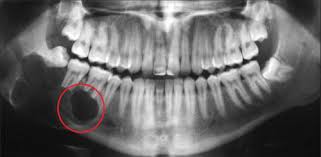

Nang chân răng (hay còn gọi là nang quanh chóp răng) là túi dịch chứa mủ hoặc mô hoại tử hình thành ở vùng chóp chân răng. Nguyên nhân chủ yếu là do vi khuẩn xâm nhập từ tủy răng viêm, chấn thương hoặc điều trị tủy không triệt để. Nang có thể phát triển âm thầm trong nhiều tháng, thậm chí nhiều năm mà không có triệu chứng rõ rệt.

Nếu không được điều trị, nang có thể phát triển lớn, phá hủy xương hàm, gây tiêu xương ổ răng, thậm chí lan sang các răng kế cận.

Chụp phim X-quang 3D Conebeam CT để xác định vị trí và kích thước nang.